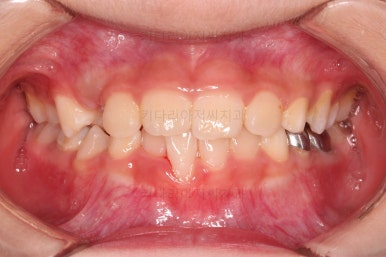

CASE 1.

나이 : 9세

총 치료기간 : 3개월

초진 시 얼굴사진인데요.

우선 중요한 건 진짜 주걱턱이냐 아니냐가 중요해요.

이번 환자분은 다행히 뼈의 문제는 없는 것으로 판단이 되었는데요.

그래서 이번 환자분도 뼈의 문제는 없지만 앞니가 거꾸로 물리는 건 개선해주자고 했죠.

바로 전후 비교사진 올립니다.